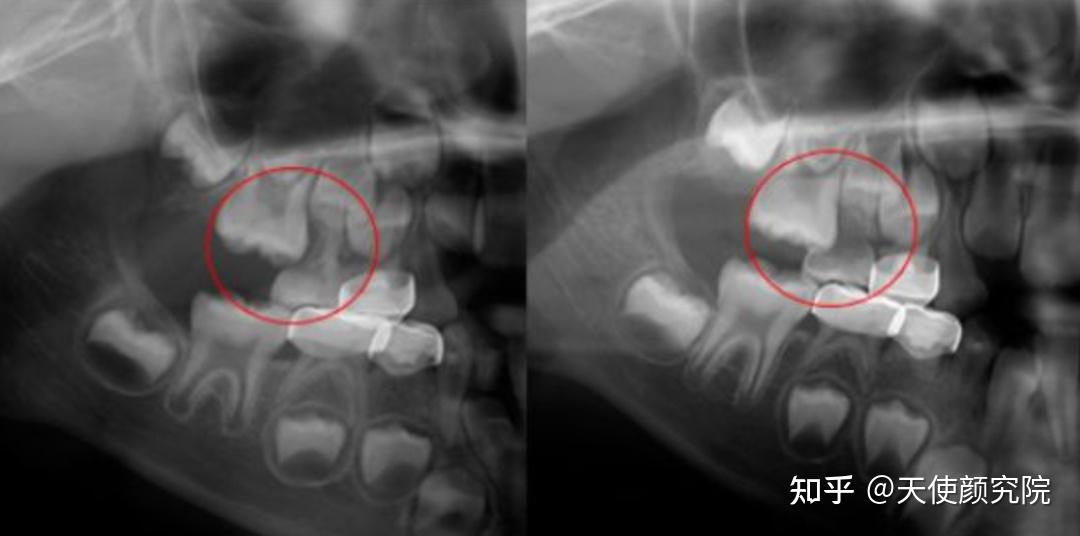

地包天一般为三类:牙性地包天、功能性地包天、骨性地包天。

牙性地包天,就是下前牙咬在上前牙的前面,通俗说就是下牙包住了上牙,表现出来就是前牙内陷,多见于于乳牙期。

牙性地包天的上下颌骨关系没有明显异常,下颌的形态、大小基本正常。

功能性地包天,上下颌骨大小形态及口腔姿势基本正常,只是牙齿咬合时,下颌功能性的过度前伸,造成了前牙反合,多见于乳牙列期和替牙期。

简单说就是青少年存在口腔不良习惯或咬合干扰,造成了下颌习惯性往前伸,形成了假性下颌前突,这种情况如果不及时矫治,会发展成骨性下颌前突。

骨性地包天,是上颌骨发育不足或下颌骨发育过度引起的前牙反覆盖关系。

因为骨性地包天和功能性地包天表现出来的形态相似,所以很多人区别不开。

简单区分法:1、上下前牙能否对齐;2、对齐时侧貌没有异常,满足这两点就是功能性地包天。

所以儿童的早期干预真的很重要,我们要做的就是在牙性和功能性阶段(乳牙6个月到6岁之间和替牙期6岁-12岁)矫治,可以有效避免影响到骨骼发育。